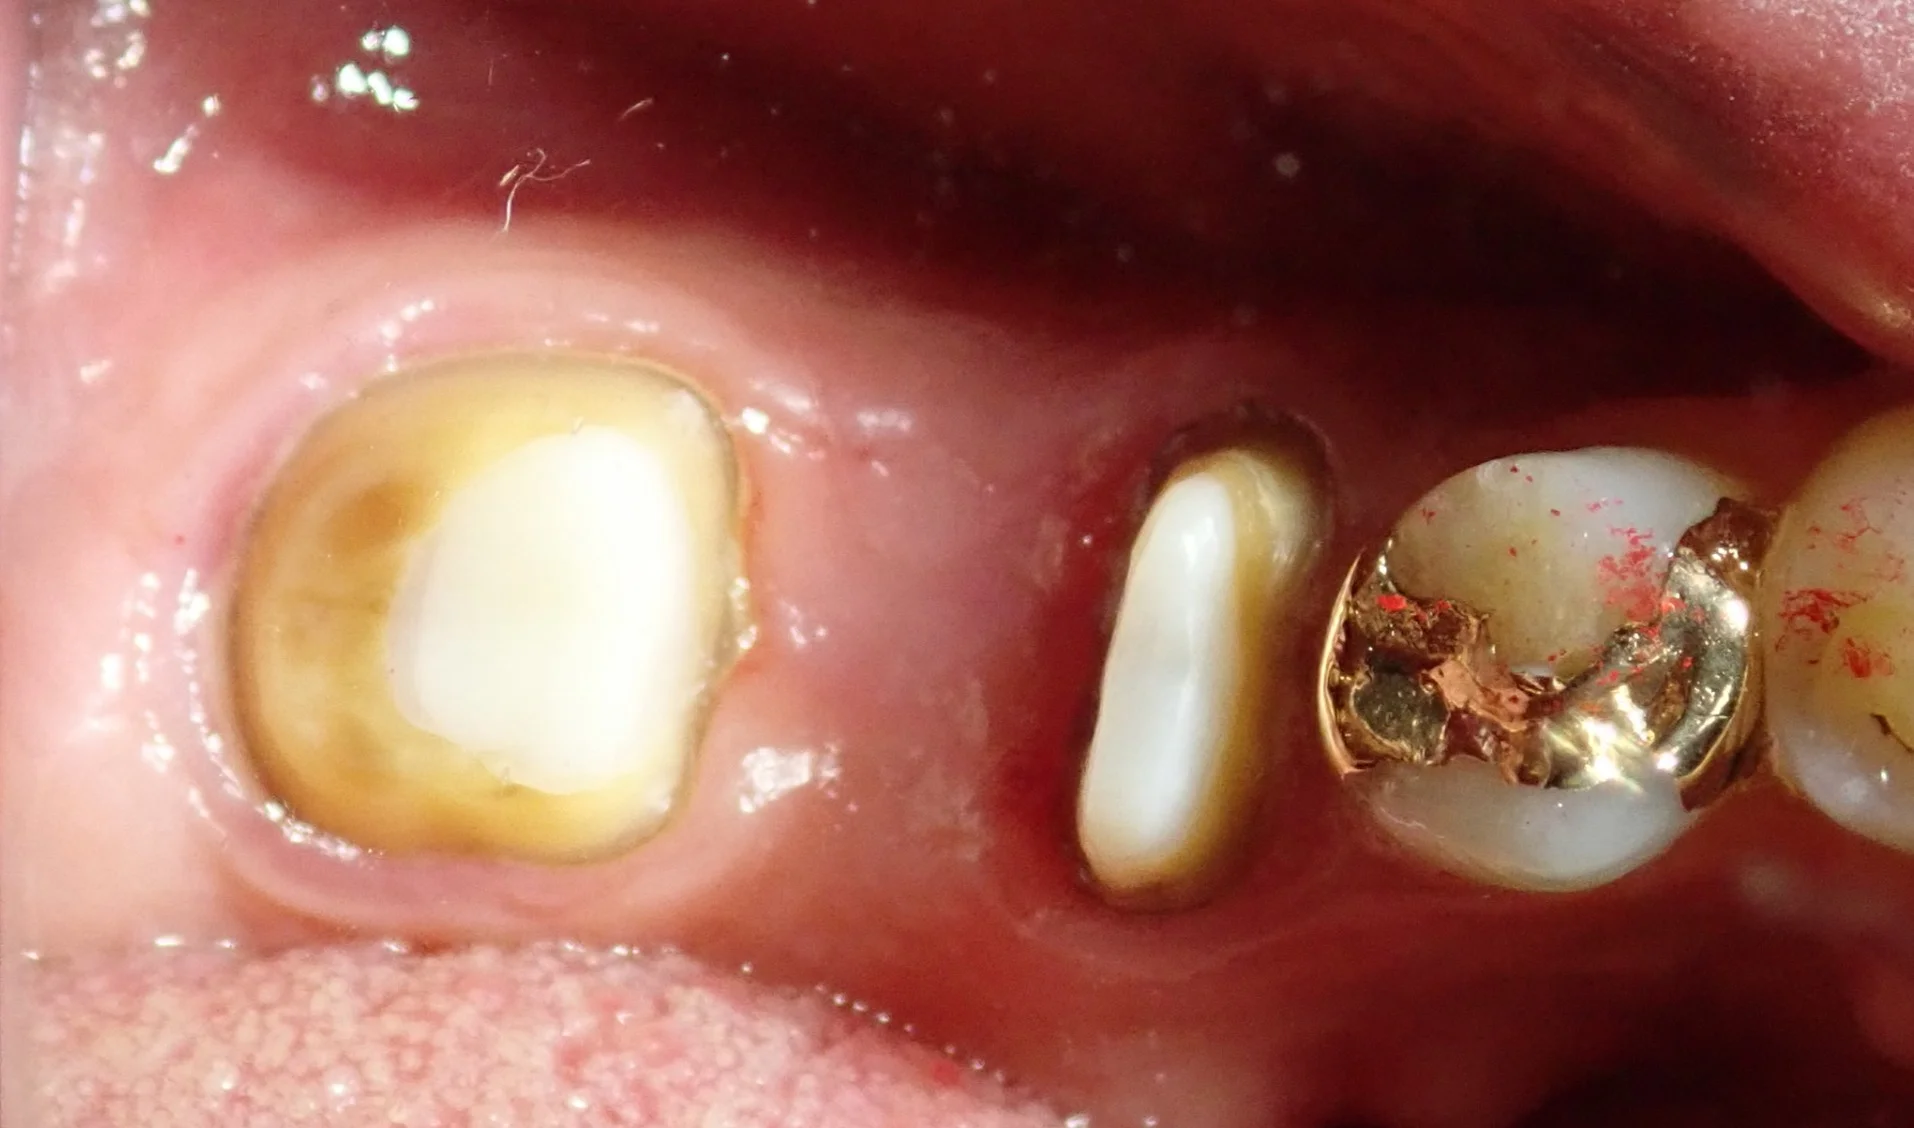

こちらの方は私が治療に入った時にはファイバーコアが入っていましたが・・・

その前は太いメタルコアが入れられていたそうです。

実際に被せ物を除去して根の状態を直接肉眼で確認したところ、後ろ側の根がレントゲンには写らないラインで真っ二つに折れていました。

ただし、ここで待っていただきたいのが・・・

写真のような根が2つある歯についてです。

折れているのがどちらか一方であれば、もう一方はまだ温存できる状態になります。

なので、こんな感じで一本だけ抜歯すれば、手前の根は残すことが出来るようになります。

無事に神経の治療も終わり、後ろの根の抜歯後の傷も問題なく治ったため、最終的な被せ物に移行することとなりました。

実際のお口の中の写真がこちらです。